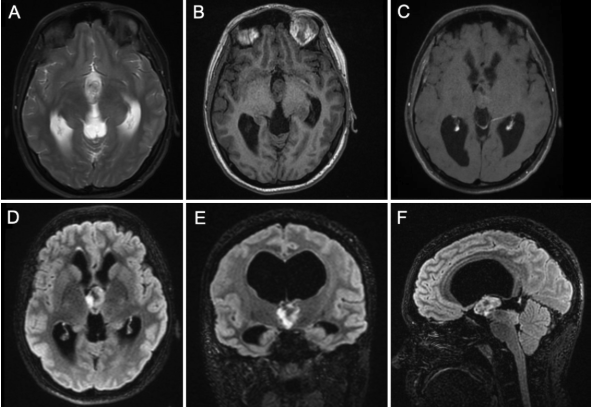

Back when we were just starting as the Class of 2024, our grad year seemed so inestimably far away it was almost a joke to say. Yet here we are, somehow now less than 6 months to go. Happy New Year, everyone. May all your post op scans be without residual in 2024.